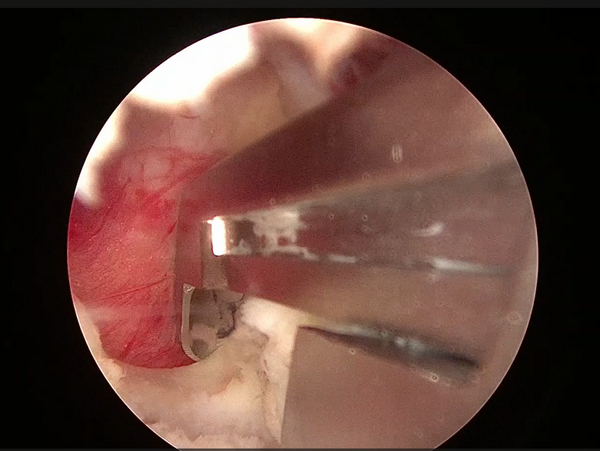

髓核摘除前后对比

切除后黄韧带和椎间盘髓核组织

患者接受手术治疗,术中仅通过两个长约0.5cm及1cm的手术切口,置入脊柱内镜及操作器械,逐步扩大“狭窄的椎管”并顺利摘除“脱出的椎间盘组织”,解除神经受压情况。